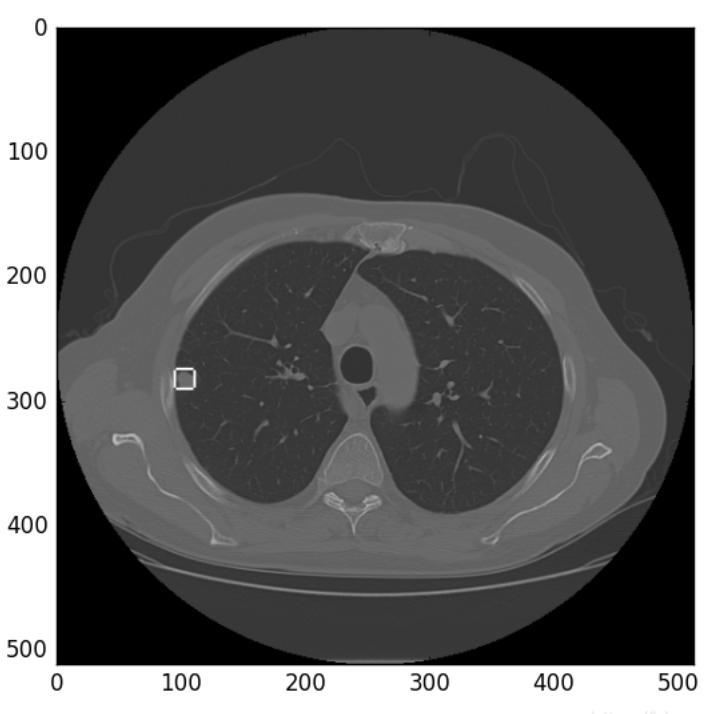

让我们一起可视化看下效果。

def show_nodules(ct_scan, nodules,Origin,Spacing,radius=20, pad=2, max_show_num=4): # radius是正方形边长一半,pad是边的宽度,max_show_num最大展示数

plt.imshow(data, cmap='gray')

plt.show()

b = np.array([[-116.2874457,21.16102581,-124.619925,10.88839157],[-111.1930507,-1.264504521,-138.6984478,17.39699158],[73.77454834,37.27831567,-118.3077904,8.648347161]])

show_nodules(numpyImage,b,OR,SP)

可视化之后的结果如下所示